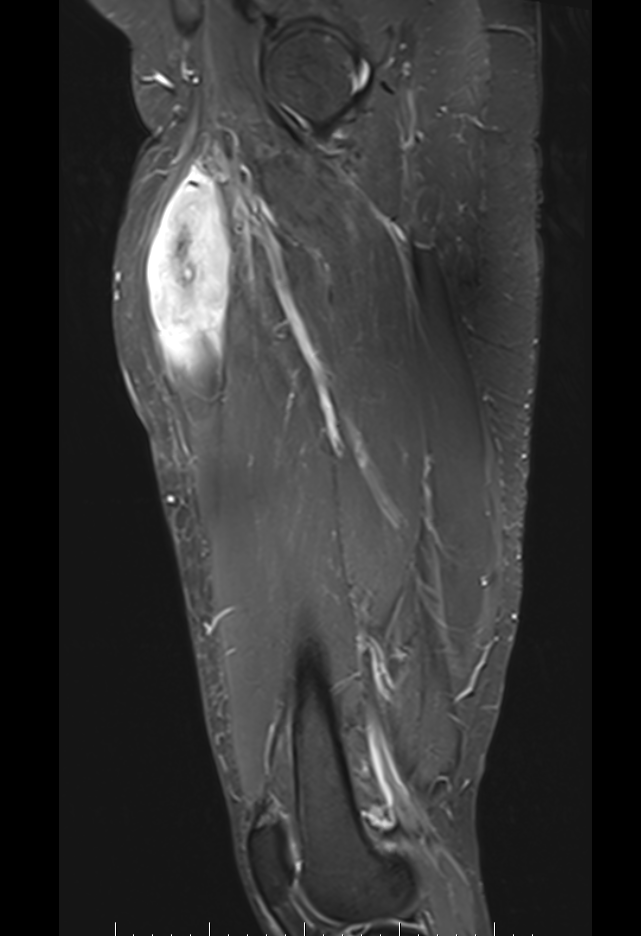

Liposarcoma posterior thigh

LS 3LS 2LS 1

MRI

Deep to fascia / heterogenous